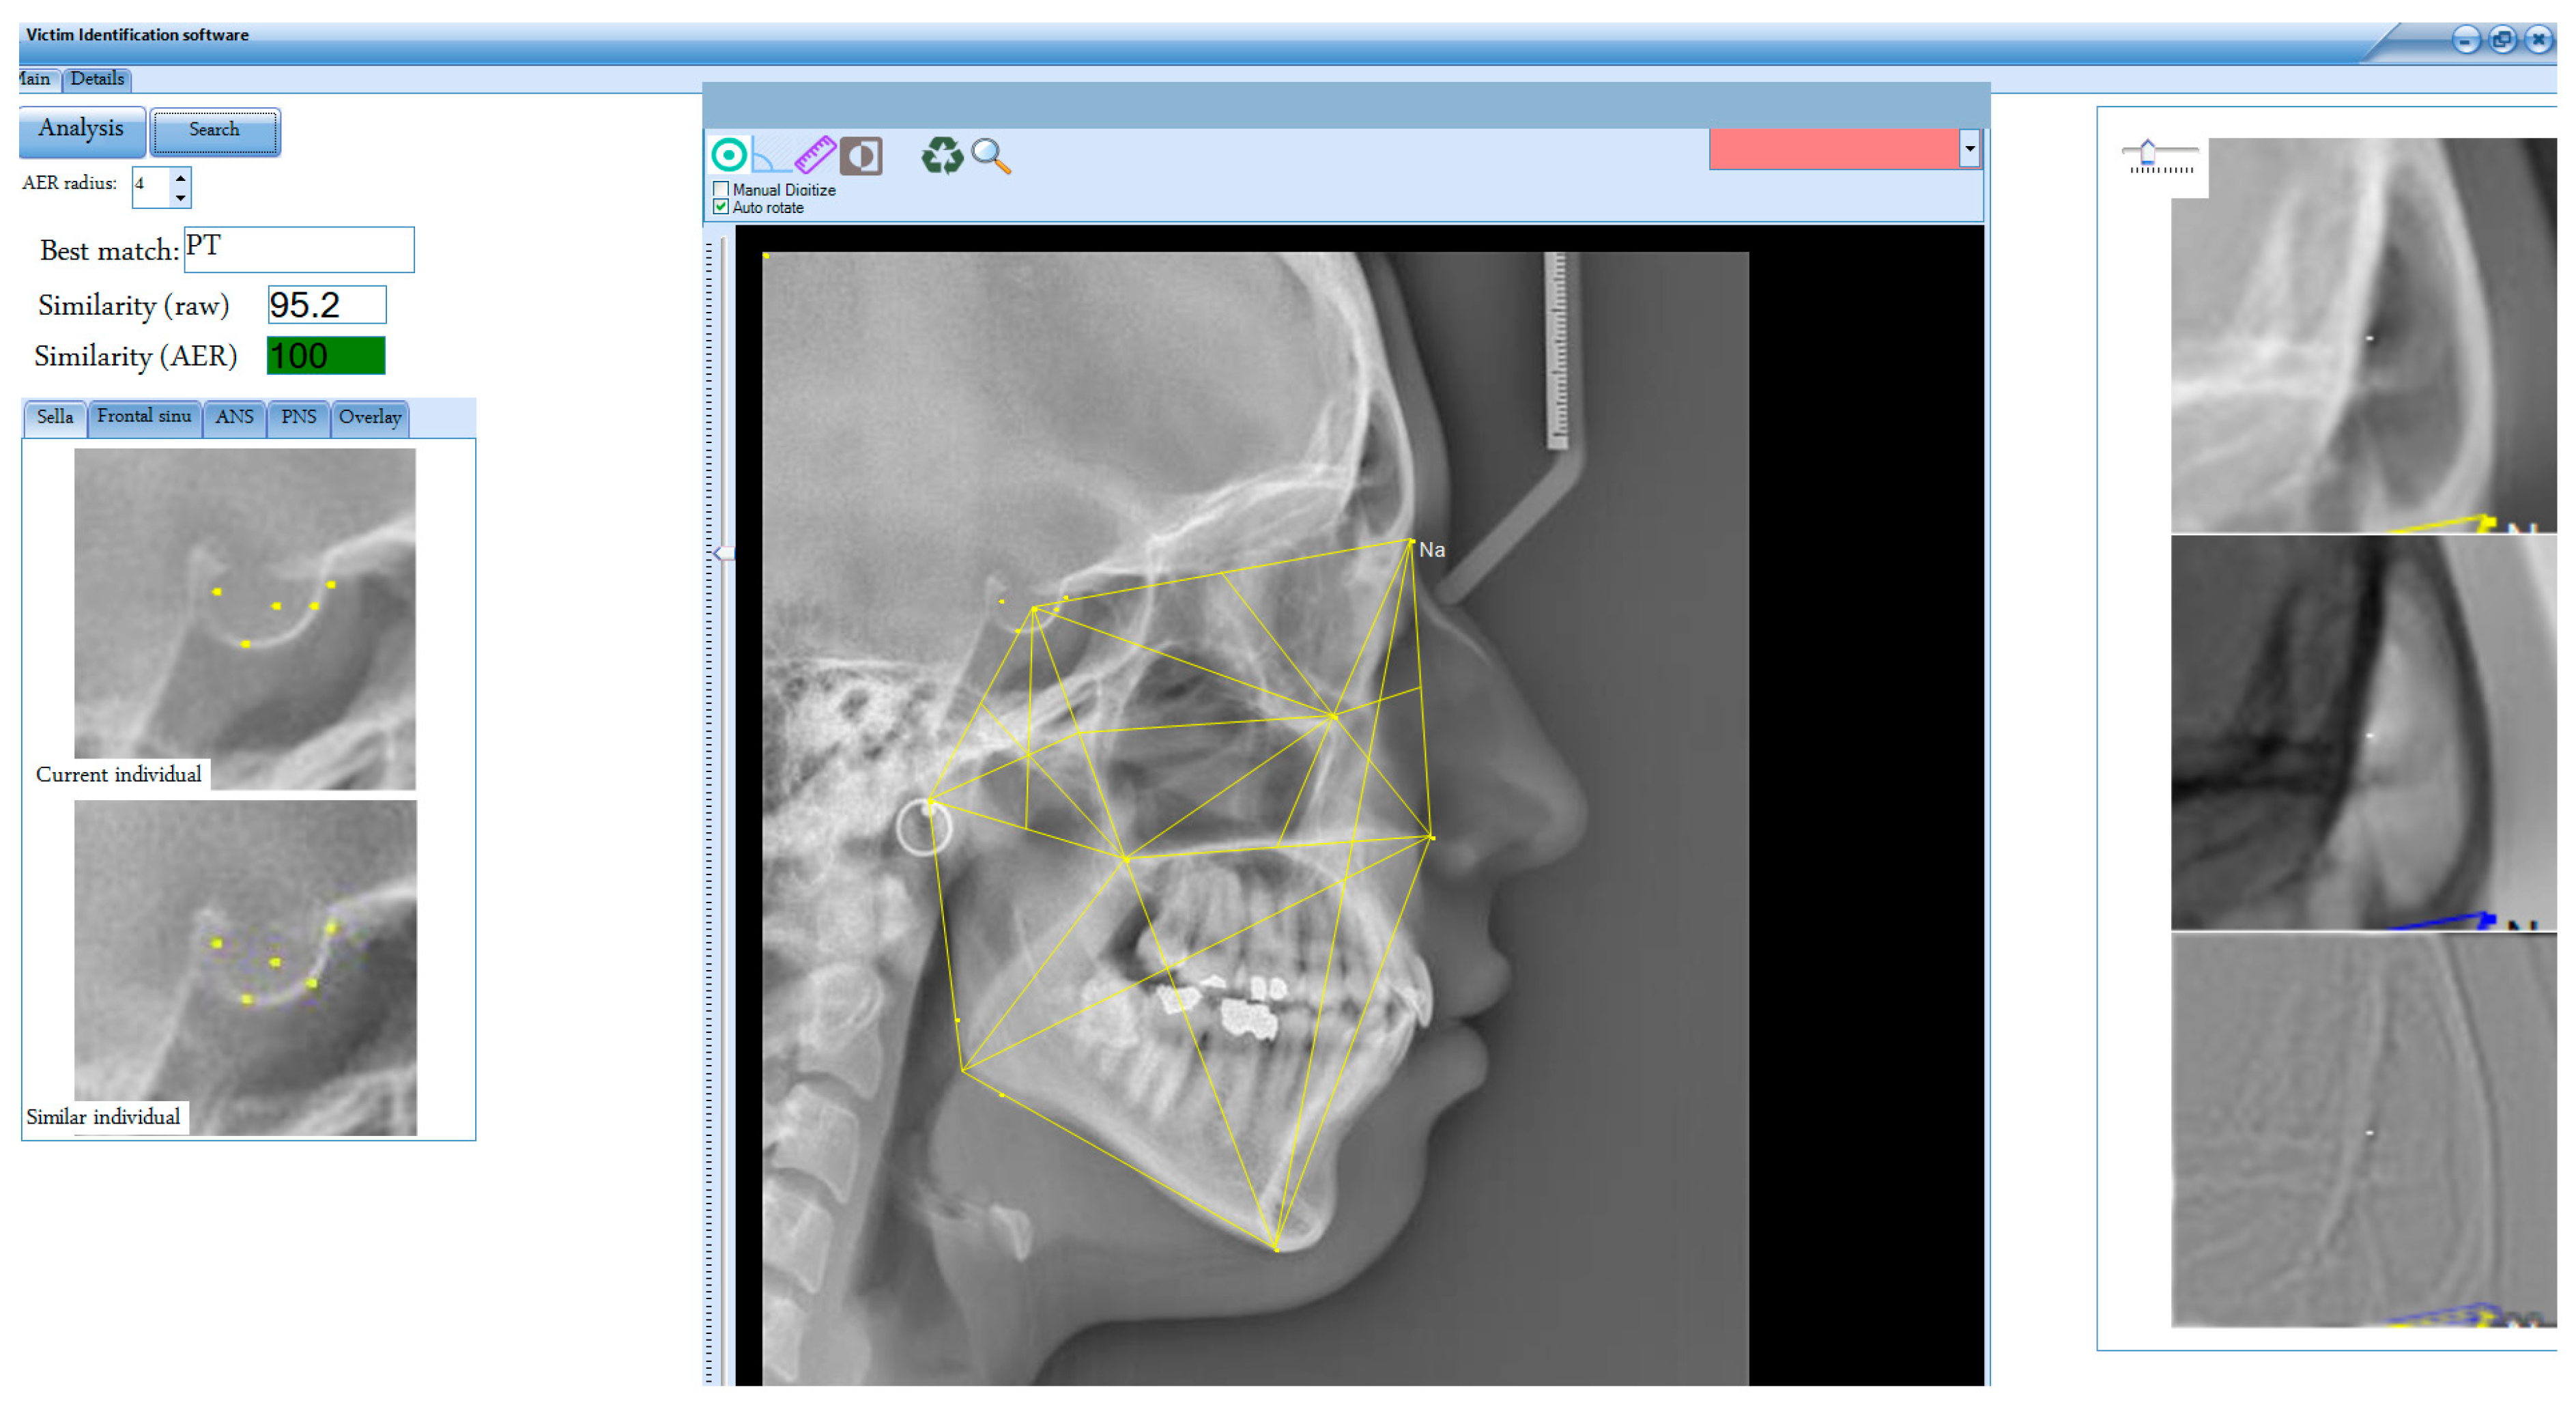

A software application was developed using C# in Microsoft Visual Studio 2019 to implement the K-VIN algorithm (Figure 5). Initial testing of the algorithm was conducted using a dataset of 400 pre- and post-treatment digital cephalograms of orthodontic patients (living individuals). Due to the lack of an AM cephalogram archive for deceased individuals, we used cephalograms from an orthodontic archive at a dental clinic. Pre-treatment cephalograms were designated as AM, and post-treatment cephalograms were designated as PM.

Figure 5.

User interface of the software developed in this study. The application automates all stages and processes (excluding key point selection). It provides outputs such as the best match, similarity scores (before and after AER), and a sorted list of the closest matches and displays anatomical landmarks for both the current and similar individuals (e.g., frontal sinus) to verify identity recognition.